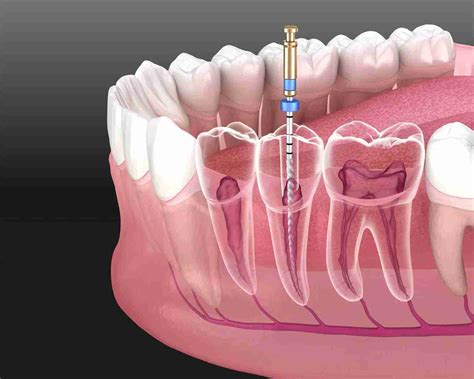

3. Accessing the Pulp: A small hole is made in the crown of the tooth to gain access to the infected pulp chamber.

4. Cleaning and Disinfection: The infected pulp is carefully removed, and the canals are cleaned, shaped, and disinfected using specialized tools.

5. Filling and Sealing: The hollowed-out canals are filled with a biocompatible material called gutta-percha to prevent future re-infection.

6. Restoration: The access hole is sealed with a temporary or permanent filling, and in most cases, a dental crown is placed later to restore the tooth's structure and function.